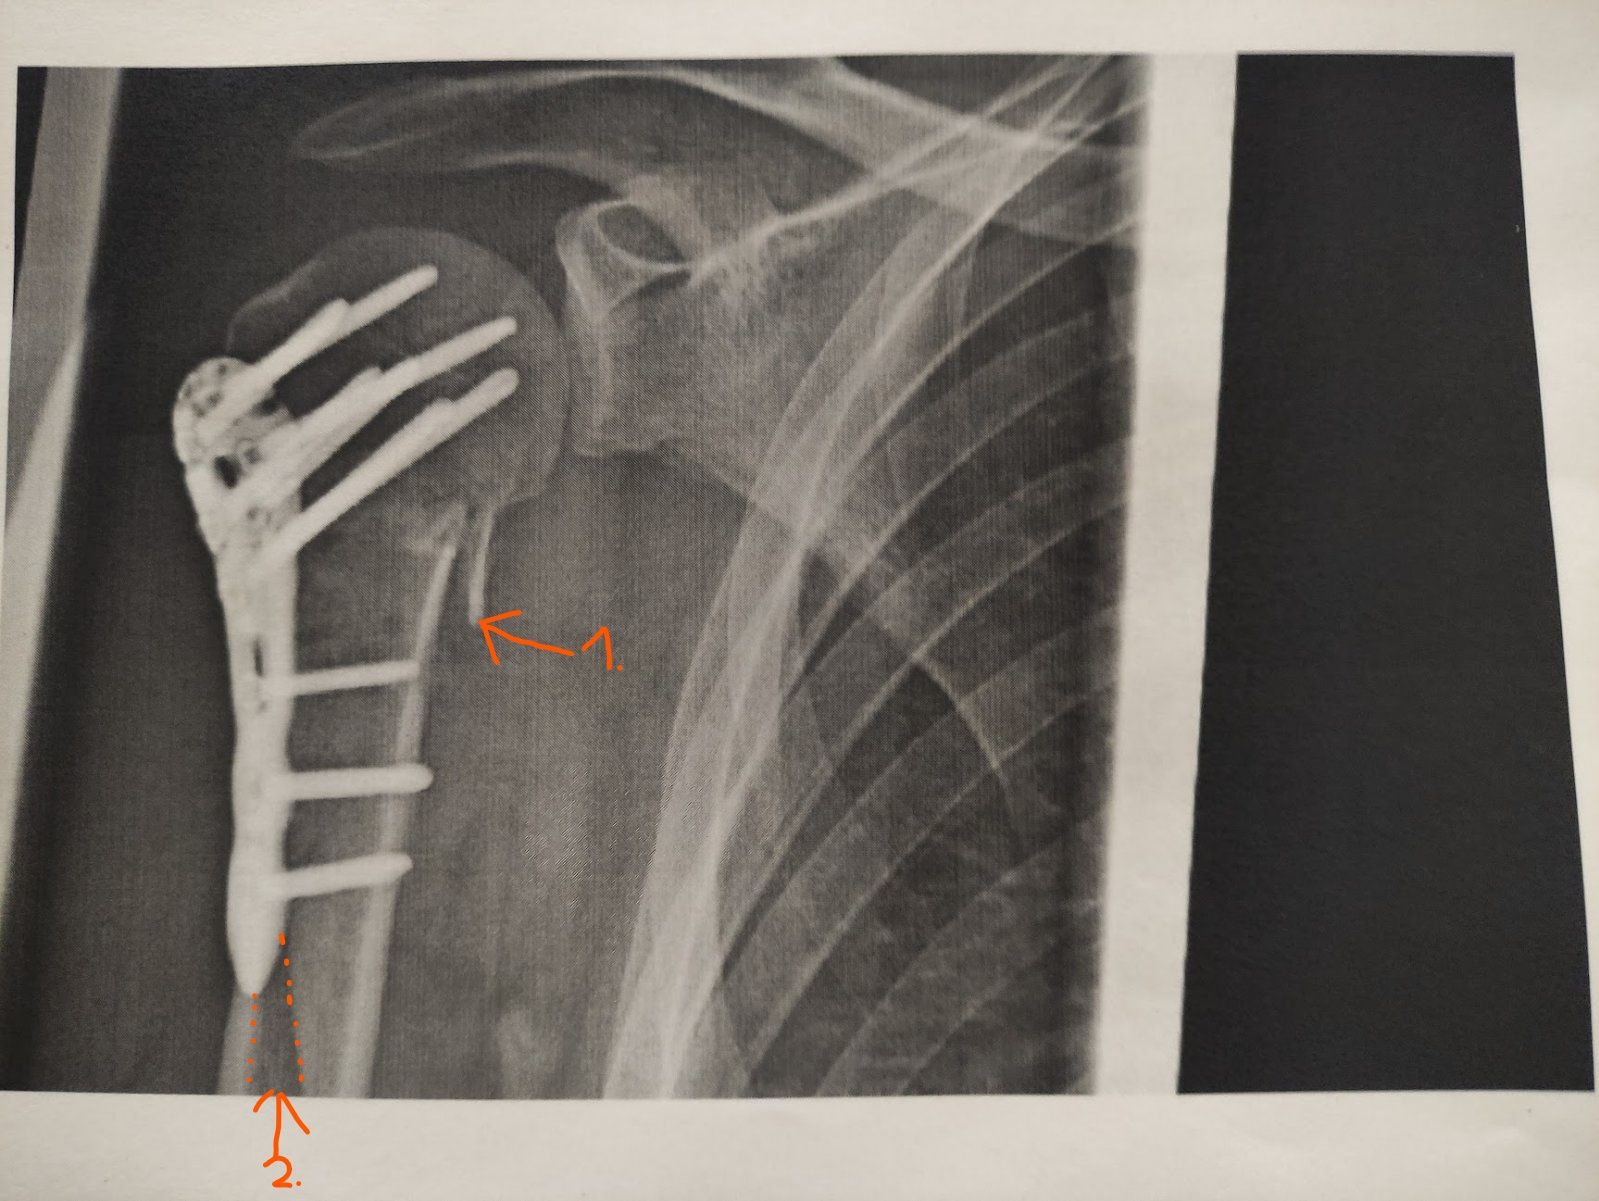

Auf der ersten Aufnahme (Seite 3) stand bei 1. etwas vom Knochen ab, was bei der neuen Aufnahme jetzt wieder am Knochen dran ist. Bei 2. war auf dem ersten Bild ein dunkler Streifen zu sehen, der bei der neuen Aufnahme nicht mehr zu sehen ist. Allerdings ist das ganze schwer zu vergleichen, auf der älteren Aufnahme sieht man die Stabilisierungsplatte etwas schräg seitlich, auf der zweiten Aufnahme genau von der Seite.

Hier nochmal zum Vergleich die alte Aufnahme:

Anhang anzeigen 952916